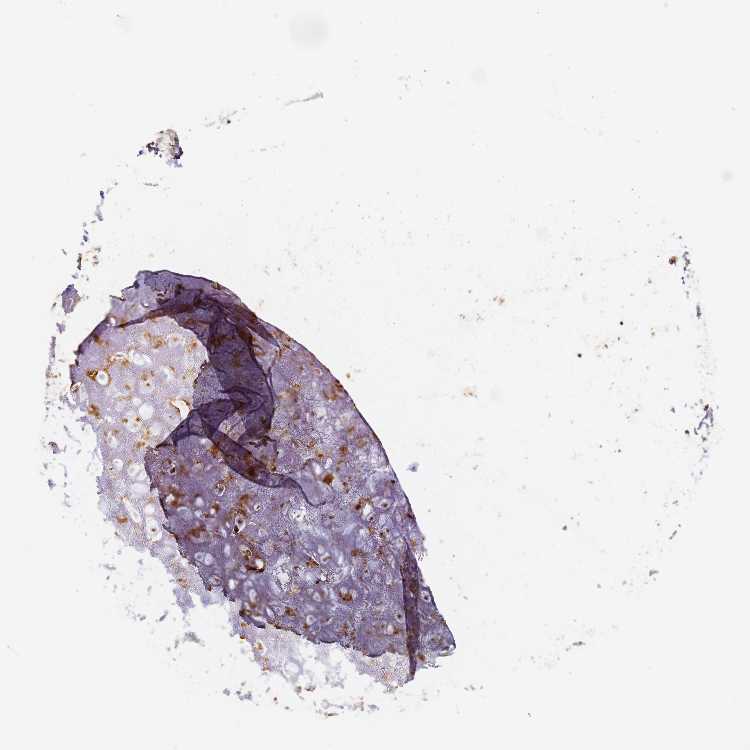

ADIPOSE TISSUE - Antibody stainingi

Antibody staining in the annotated cell types in the current human tissue is reported as not detected, low, medium, or high, based on conventional immunohistochemistry profiling in selected tissues. This score is based on the combination of the staining intensity and fraction of stained cells.

Each image is clickable and will lead to virtual microscopy that enables deeper exploration of all samples and also displays staining intensity scores, fraction scores and subcellular localization as well as patient and tissue information for each sample.

Antibody HPA044968

Adipocytes Medium